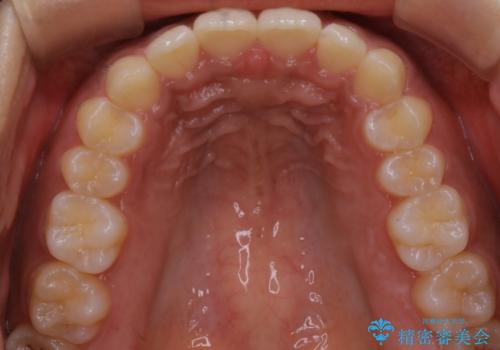

インビザライン矯正 歯を抜かずに出っ歯を改善!

- 出っ歯と前歯の隙間が空いていることを気にされて来院されました。

また、自然な感じで口元を下げていとのことでした。

奥歯のかみ合わせが問題なかったため、上顎の前歯の隙間を閉じるとともに、上顎の歯の側面を削ることをメインにして、出っ歯を改善する治療計画としました。

上顎の歯の傾きを変えるうえで、下顎の歯とのバランスのことも考え、下顎の歯の側面も削ることを加えています。

また、今回は口元を変えたい中に、劇的な変化は避けたいとのことだったので、抜歯をしない計画としています。

抜歯をしない場合、口元の変化は感じにくいですが、前歯の傾きが変わることで、口の閉じやすさは感じていただけたとのことです。

症例にもよりますが、本症例は奥歯のかみ合わせに問題がなかったので歯の側面を削ることメインに、前歯の傾きを改善することができました。

抜歯を行う場合や抜歯をしなくても奥歯の位置をずらす場合は、治療期間が長期化することが多いですが、今回は歯を削ることで改善できたため、短期間で治療を完了することができました。